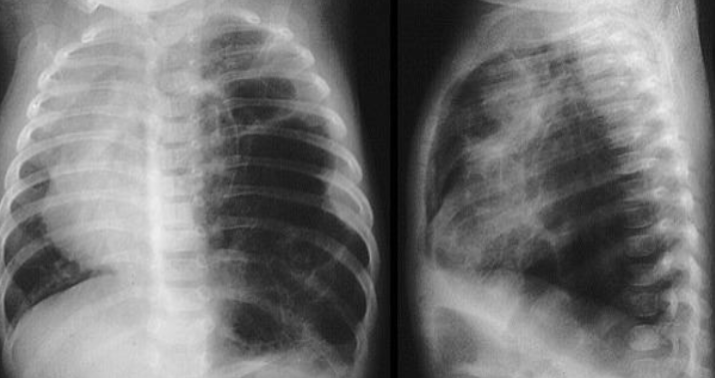

- AP chest film which shows opacification of the middle and lower zones of - (1 .the left lung. The upper border of the opacity is concave

- .This indicates pleural effusion (PE) - (2

- After inserting chest tube, pus was coming out. This means that the PE is - (3 .an Empyema

- .The cause of this empyema is most likely a Bacterial Pneumonia - (4

- The age of the patient is an 8 years which means that the most likely - (5 .organism is Streptococcus Pneumonae